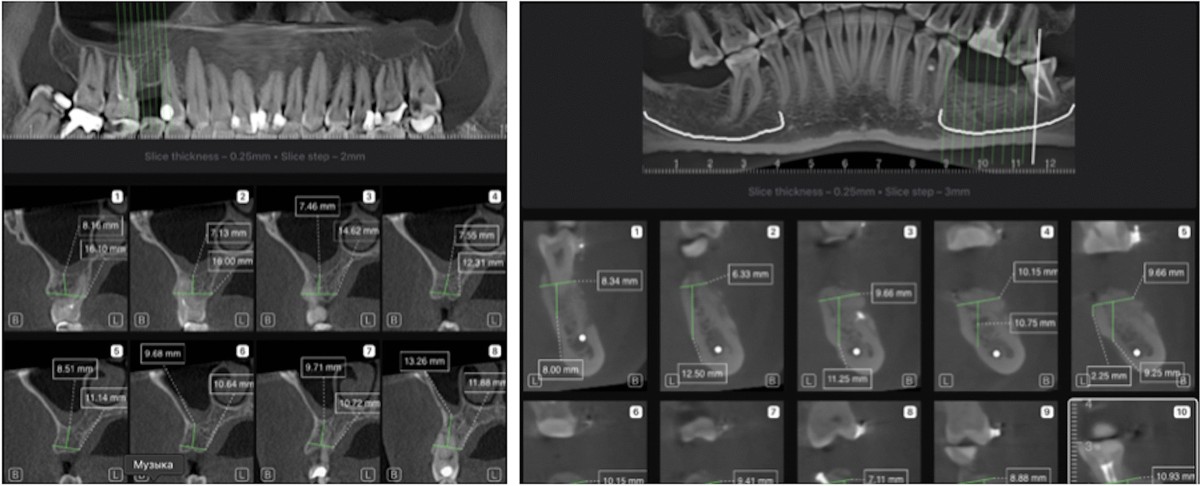

Pajisjet CBCT (“Cone Beam Computed Tomography”) tashmë janë baza për implantologji, kirurgji orale, dhe trajtime të tjera të avancuara. Kuptohet si “standard i artë” në diagnostikim për implantet.

Avantazhe: mund të shohësh strukturën kockore, nervat, pozicionin e implantit në 3 dimensione – redukton surprizat intra-kirurgjikale.